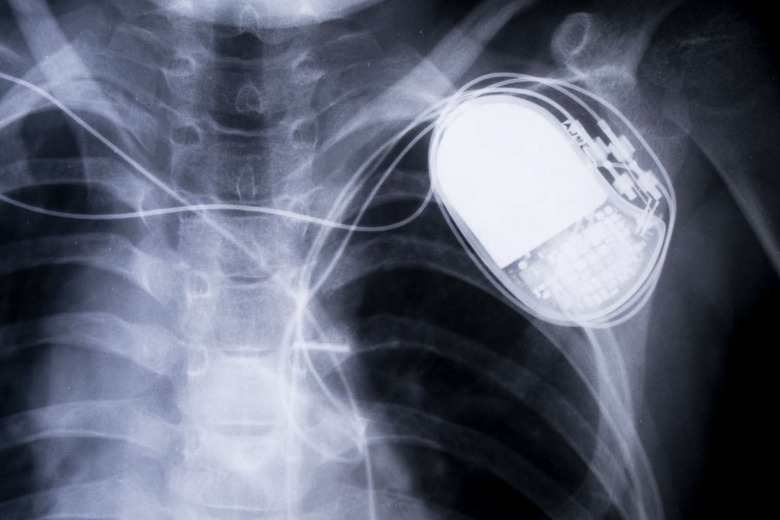

Authorities from Ohio arrested a man named Ross Compton and charged him with arson and insurance fraud based on his pacemaker data. Compton told the police that when he saw his house burning on September 19th last year, he packed his suitcases, threw them out his bedroom window and carried them to his car. However, since has a serious heart condition and other medical issues that would have made it extremely difficult for him to do all those, the cops were able to secure a search warrant for his pacemaker data.

According to court documents, a cardiologist who reviewed his heart rate, pacer demand and cardiac rhythms before, during and after the fire said:

"...it is highly improbable Mr. Compton would have been able to collect, pack and remove the number of items from the house, exit his bedroom window and carry numerous large and heavy items to the front of his residence during the short period of time he has indicated due to his medical conditions."

That data became a key piece of evidence that allowed law enforcement to indict the accused, though they also detected gasoline on his shoes and clothing. The fire ended up causing $400,000 in damages. Whether or not Compton is truly guilty, Electronic Frontier Foundation staff lawyer Stephanie Lacambra told SC Magazine that cases like this "could be the canary in the coal mine concerning the larger privacy implications of using a person's medical data."